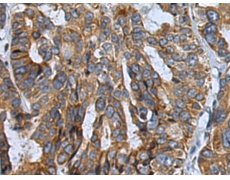

IHC Recommend dilution: |

50-200 |

IHC positive control: |

Human cervical cancer |